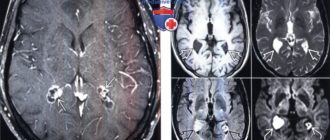

Двусторонние кисты хороидных сплетений боковых желудочков мозга

Кисты сосудистых сплетений головного мозга у плода: причины, последствия Второй плановый ультразвуковой скрининг при